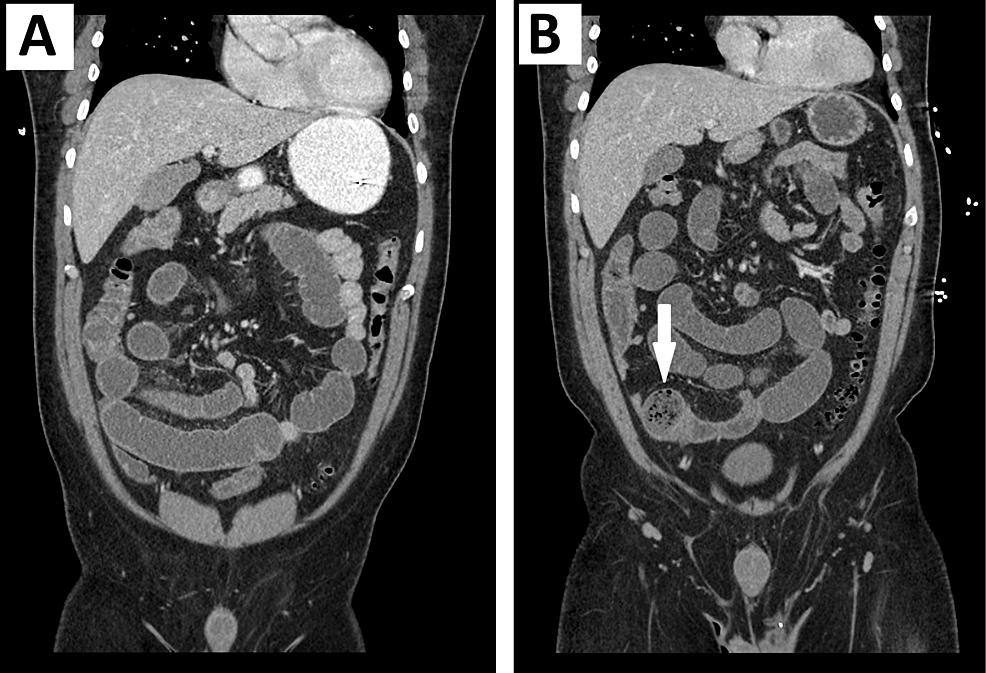

From www.researchgate.net

(PDF) Endoscopic and Radiographic Findings and Operative Treatment of a Mechanical Ileus Dog gastrointestinal (gi) motility disturbances are widely underrecognized in dogs and cats, primarily because we do not have good tools to diagnose them. Diagnosis is based on signs, clinical. gi obstruction is an emergency condition and has a range of causes. the two major types of ileus are obstructive (mechanical) and functional. objective evaluation of mechanical obstruction. Mechanical Ileus Dog.